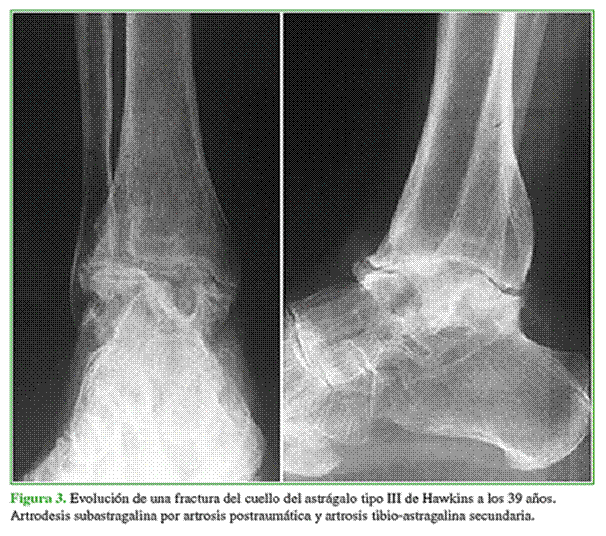

Ocho de nuestros pacientes (40%) presentaron artrosis postraumática, y la articulación subastragalina era la más afectada (Figura 3).

El compromiso articular se debe a la misma lesión producida en el momento del trauma y al daño progresivo secundario a defectos de reducción que alteran la biomecánica del pie y el tobillo. Las fracturas del cuello del astrágalo tipos III y IV son las más propensas a desarrollarla y la incidencia publicada oscila entre el 56% y el 100%.20,21 Esta incidencia aumenta conforme se prolonga el seguimiento de los pacientes, lo que nos hace pensar que todos van a desarrollar artrosis en el mediano o largo plazo.